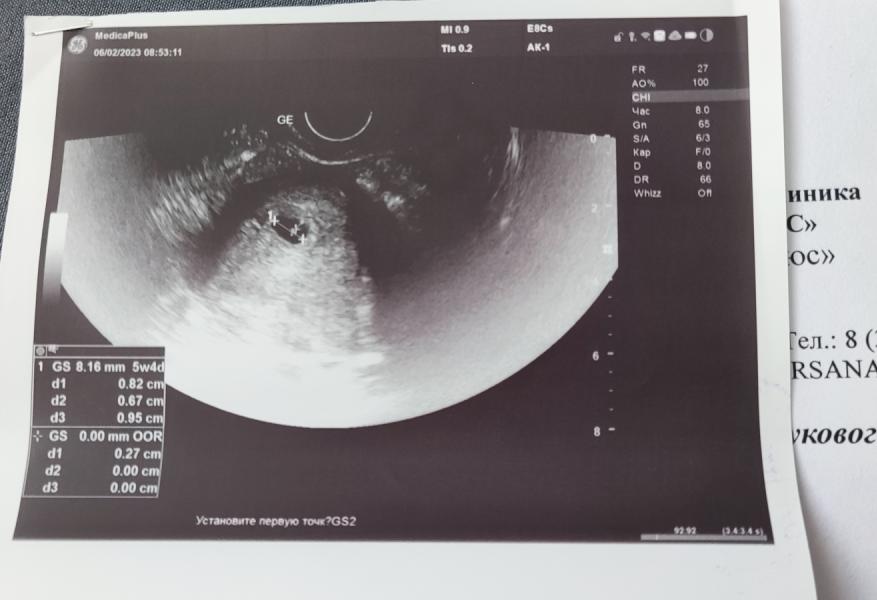

Наше первое УЗИ ♥️

06.02.2023